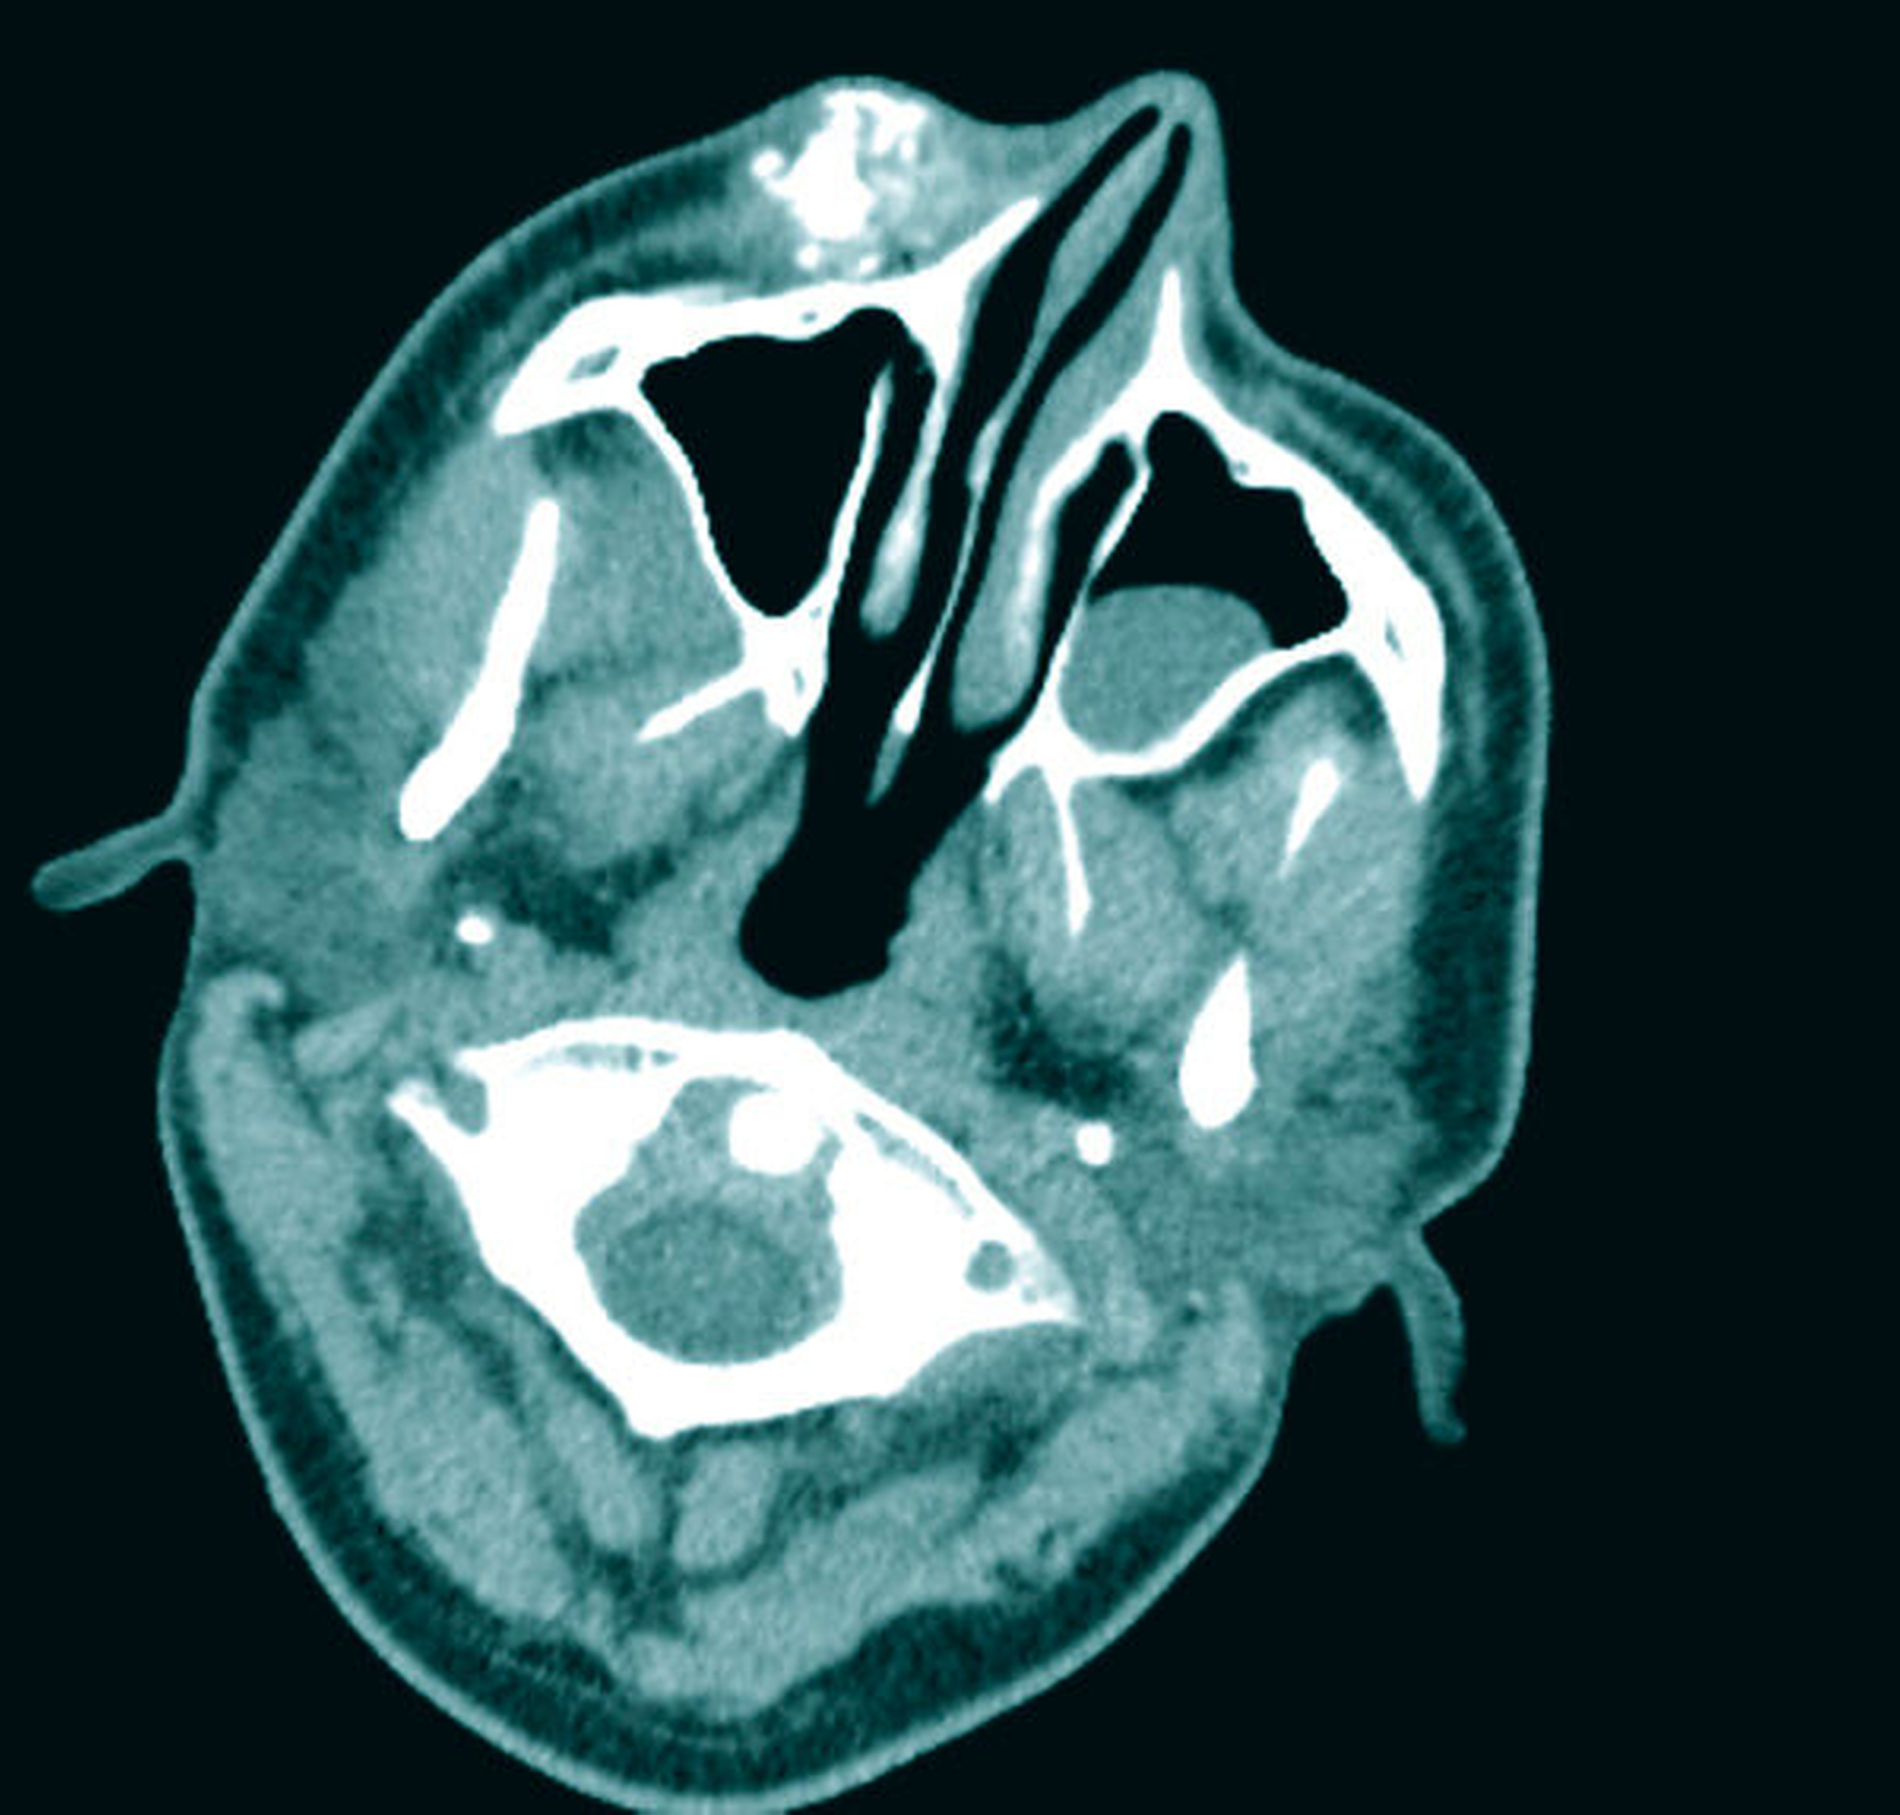

Zur Beurteilung der Befundausdehnung und zur Planung der Therapie wurde präoperativ eine Magnetresonanztomografie (MRT) des Schädels angefertigt (Abbildung 2). Hier zeigte sich die bekannte vaskuläre Malformation der rechten Wange mit Ausläufern nach intraorbital, in die Fossa pterygopalatina und infratemporalis. Im Vergleich zu den Voraufnahmen zeigte sich eine geringe Größenprogredienz des extraorbitalen Befunds (Abbildung 3).

Nach präoperativer Sklerosierung des Wangenhauptbefunds (Abbildung 4) erfolgte am Folgetag die Resektion in Intubationsnarkose. Hierzu wurde nach subziliärer Schnittführung (Abbildung 5) eine scharfe Präparation des Tumors nach kaudal unter Schonung des Ramus buccalis des Nervus facialis durchgeführt (Abbildung 6) und dieser schließlich exzidiert (Abbildung 7). In der histopathologischen Aufarbeitung zeigten sich Muskel-, Fett- und Weichgewebe mit reichlich interponierten, kavernös konfluierenden, blutgefüllten Gefäßformationen unterschiedlicher Größe (Abbildung 8). Der postoperative Verlauf gestaltete sich bis auf eine vorübergehende Einschränkung der Fazialisfunktion im Bereich des Mundastes unauffällig, sodass der Patient zeitnah in die ambulante Weiterbetreuung entlassen werden konnte.

Zur Diagnostik stehen insbesondere bildgebende Verfahren wie die Sonografie, die Computertomografie (CT) und die Magnetresonanztomografie (MRT) im Vordergrund. Sonografisch stellen sich Lymphangiome als zystische, durch Septen unterschiedlicher Dicke unterteilte Strukturen dar. Um jedoch eine exakte Aussage über die weichgewebliche Ausdehnung des Befunds treffen zu können, benötigt man eine MRT [Meinel und Daum, 1974; Giese, 2005]. Histologisch zeigen sich mit flachem Endothel ausgekleidete, erweiterte Lymphgefäße unterschiedlicher Größe ohne kapsuläre Begrenzung [Barnes et al., 2005]. Neueste Studien befassen sich mit der Frage, inwiefern sich Lymphangiome mittels Biomarkern wie MEK/ERK, BMP und Wnt/beta-catenin im peripheren Blut nachweisen lassen [Kim et al., 2019]. Die endgültige Diagnosestellung erfolgt mittels histopathologischer Aufarbeitung [Ganesh et al., 2013]. Ergänzend stehen die immunhistochemischen Marker CD31, CD34 und FVIII-rAg zur Verfügung [Burgdorf et al., 1981; Brown et al., 1999; Galambos und Nodit, 2005].